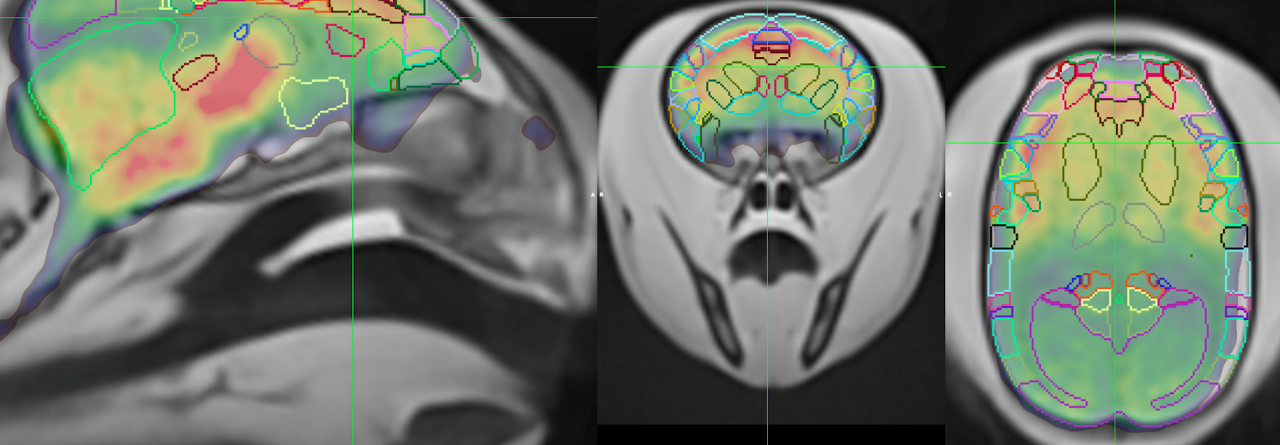

Molecular Imaging uses small amounts of radioactive tracers to image important cellular and molecular processes in living subjects, with applications in oncology, cardiology, neuroscience, immunology, theranostics, drug development and basic life science research. Bruker offers advanced hybrid imaging devices such as modular benchtop PET, SPECT, CT, or hybrid PET/CT, PET/MR and PET/SPECT/CT to help scientists and life science industry to advance their research or business.